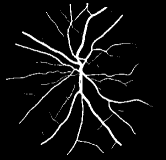

Refer to caption

Figure 1: Vessel segmentation results of side-output(s-out) layers produced by three networks. From top to bottom the network is normal DSN (with no short connections), BS-DSN (DSN with bottom-top short connections) and BTS-DSN (DSN with both bottom-top and top-bottom short connections), respectively.

As pointed out in recent works [15, 17], a good semantic segmentation network should learn multi-level features. Further, it should have multiple stages with different receptive fields to learn more inherent features from different scales. FCN, taken as an example, uses skip connections to fuse multiple stages outputs, as well as the HED network, in which a series of side-output layers are added after each stage in VGGNet. The HED network was first proposed for edge detection, and further used for image-level vessel segmentation in recent studies [6, 16], with significant performance. However, our experimental results show that such network architecture is not appropriate for vessel segmentation directly. Figure 1 provides such an illustration. Reasons for this phenomenon are straightforward. On one hand, the side-output of the first layer often contains too many noises. On the other hand, the features produced by the last side-output layer are too coarse due to information loss of pooling operation. Obviously, the inaccurate vessel map of side-output1 and side-output4 should have negative impacts on the final segmentation result.

In addition, we can observe from Figure 1 that the side-output1 and side-output4 of the BTS-DSN were more accurate compared with those of the DSN.